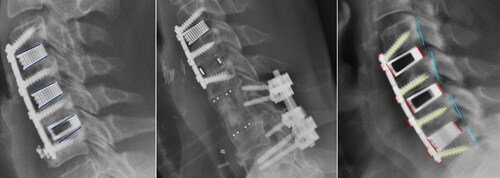

Nexus Spine's Patented Tranquil Interbody Implants Achieve Exceptional Outcomes

The results of this study suggest that Nexus Spine's patented technology amounts to a significant improvement over the competing devices...